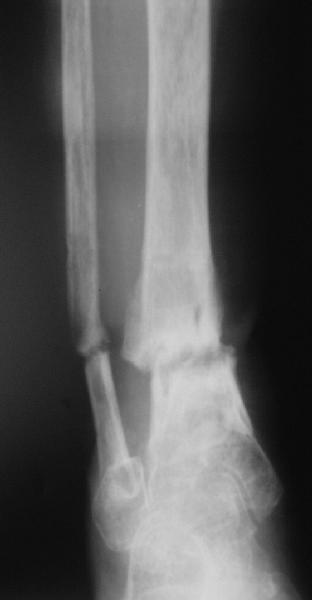

Глубокоуважаемые коллеги,Поступила женщина 72 лет. Полтора года назад - укушенная рана, перелом голени. Лечили аппаратом, не срослось. Долго не заживала рана.

Но вроде уже с полгода мягкие ткани закрыты. Спереди подпаянные рубцы. Есть приличная подвижность на уровне несращения. Картинки в приложении. Что предложите? Спсибо заранее.

Какова подвижность в голеностопе? Если движений в суставе практически нет (о чем можно предположить по Ргграмме) и инфекция исключена, я бы подумал о ретроградном штифтовании через таран.

Как ты думаешь, какова перспектива голеностопного сустава с такой исходной мобильностью? Судя по боковой проекции суставной хрящ в переднем отделе голеностопа разрушен, что при восстановлении оси голени и нагрузке приведет к ОА. Предвидеть в какой степени он будет выражен невозможно, вполне

вероятен последующий артродез.